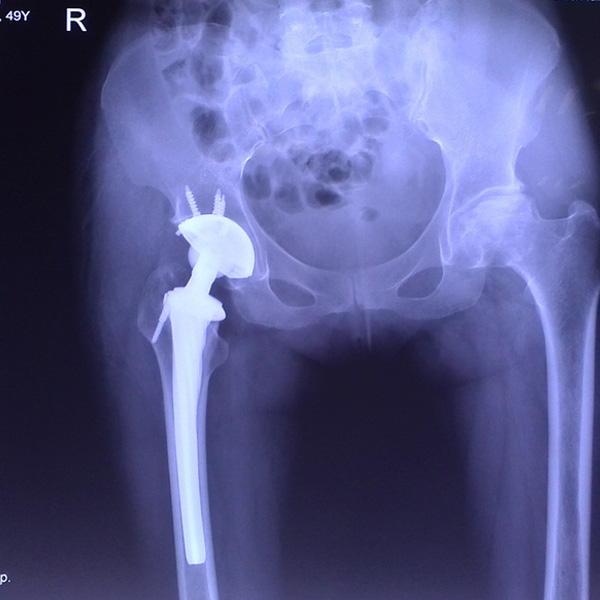

• 髖關節翻修髖關節翻修手術后手術前

髖關節翻修

患者蘇某,女性,11年前因“左髖關節屈曲攣縮畸形”行左側人工全髖關節置換,近來感覺左髖關節疼痛,不敢行走,經“攜生醫療平臺”就診于哈......